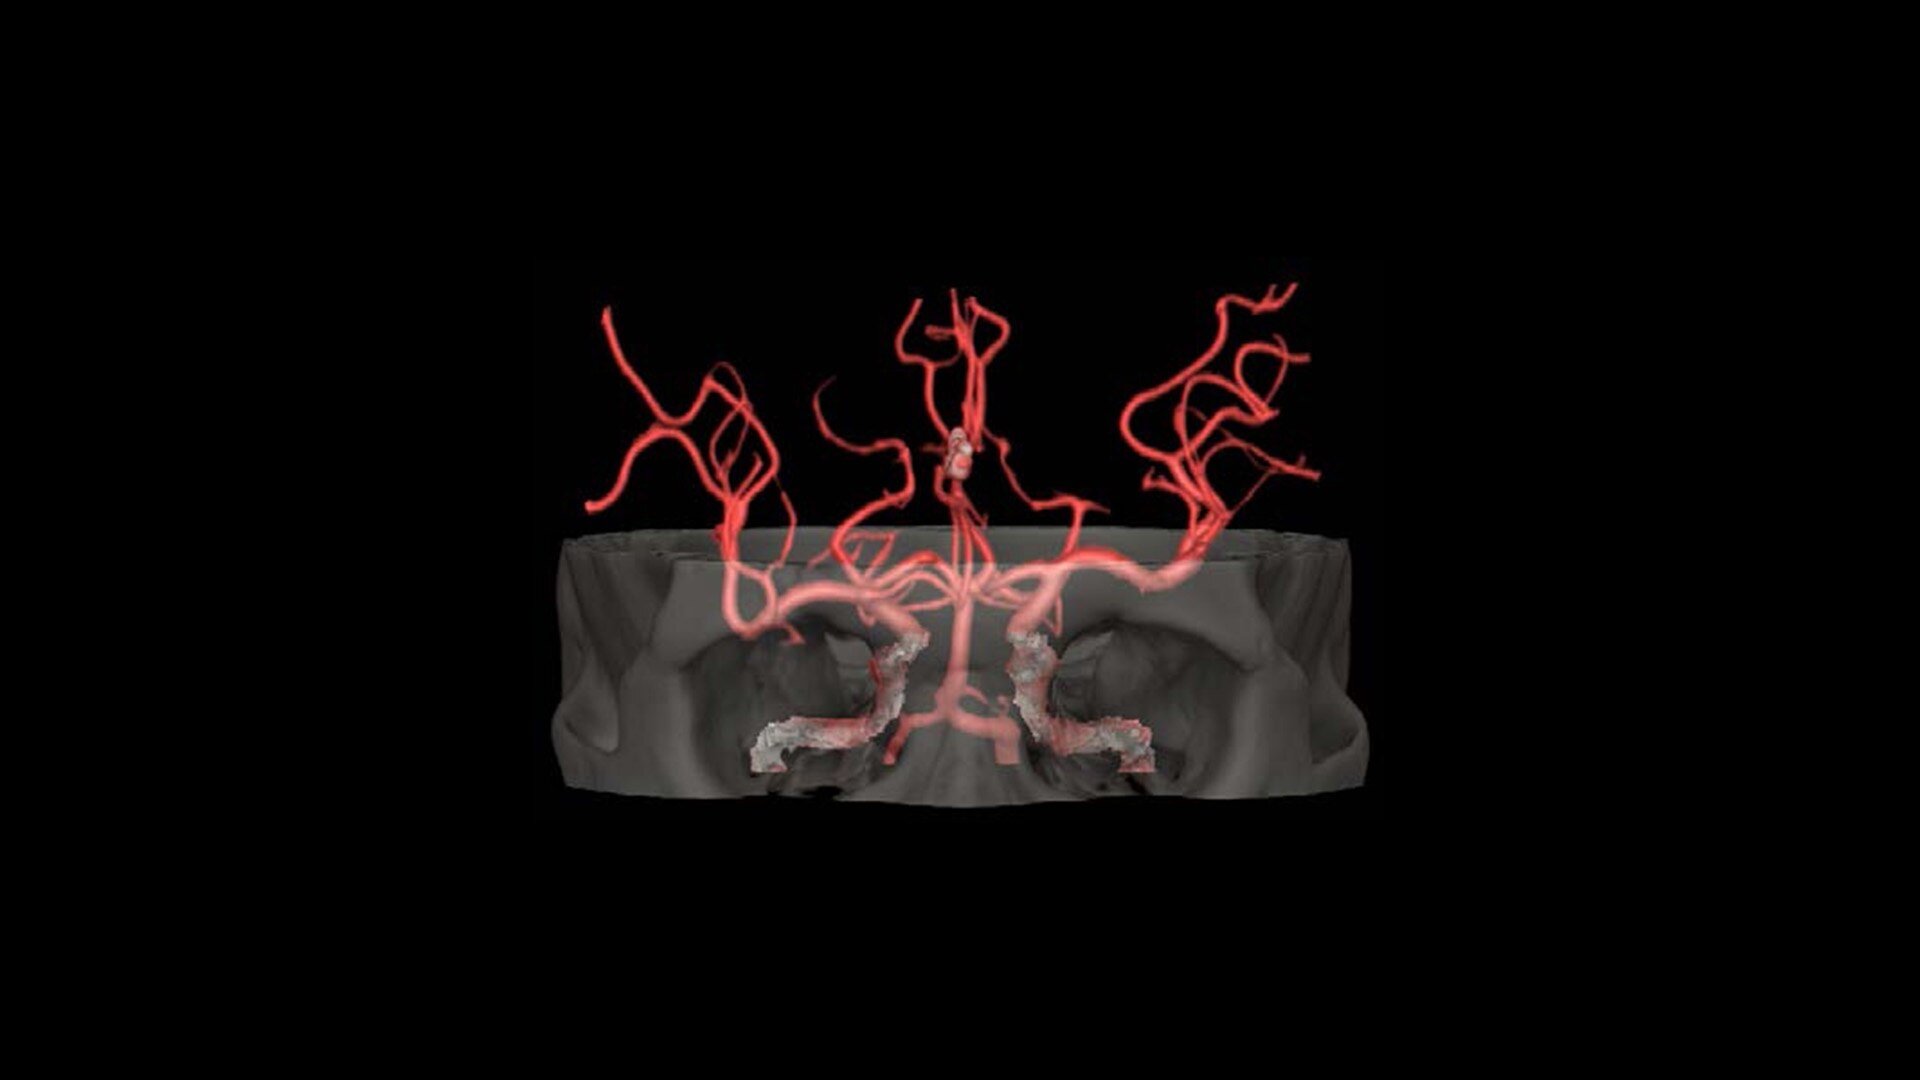

Advanced Visualization

Elevate your CT imaging with our collection of advanced visualization applications that assist reading, automate post-processing and streamline imaging review.